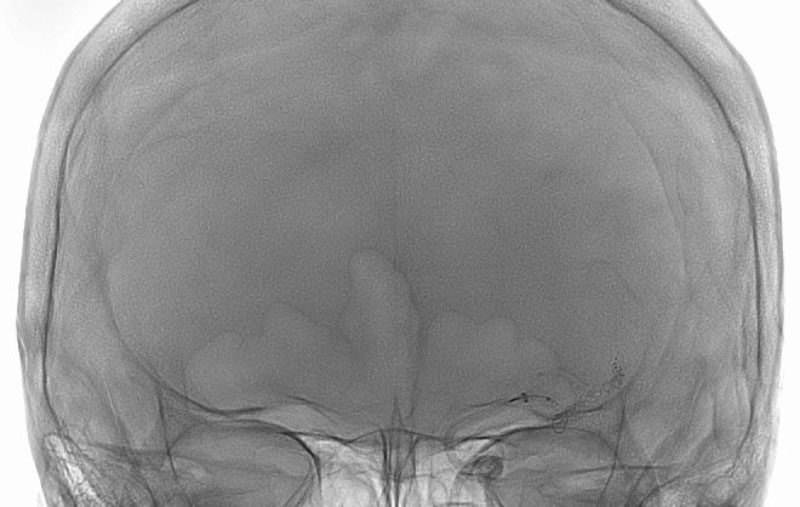

No.1596 手術前